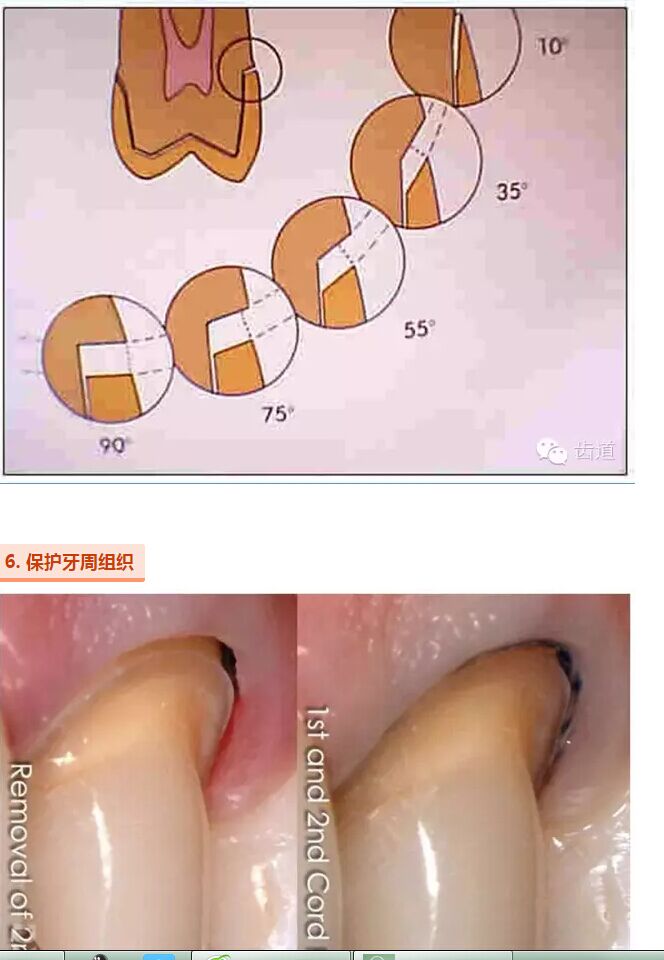

牙的外形及洞形的幾何形狀:主要是牙體制備出一定聚合角度產(chǎn)生的阻擋作用